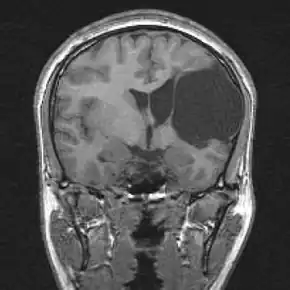

| Porencephalic cyst in the left parietooccipital and right frontal area.[1] | |

Cysts or cavities can occur anywhere within the brain and the locations of these cysts depend highly on the patient. Cysts can develop in the frontal lobe, parietal lobe, forebrain, hindbrain, temporal lobe, or virtually anywhere in the cerebral hemisphere.[8]